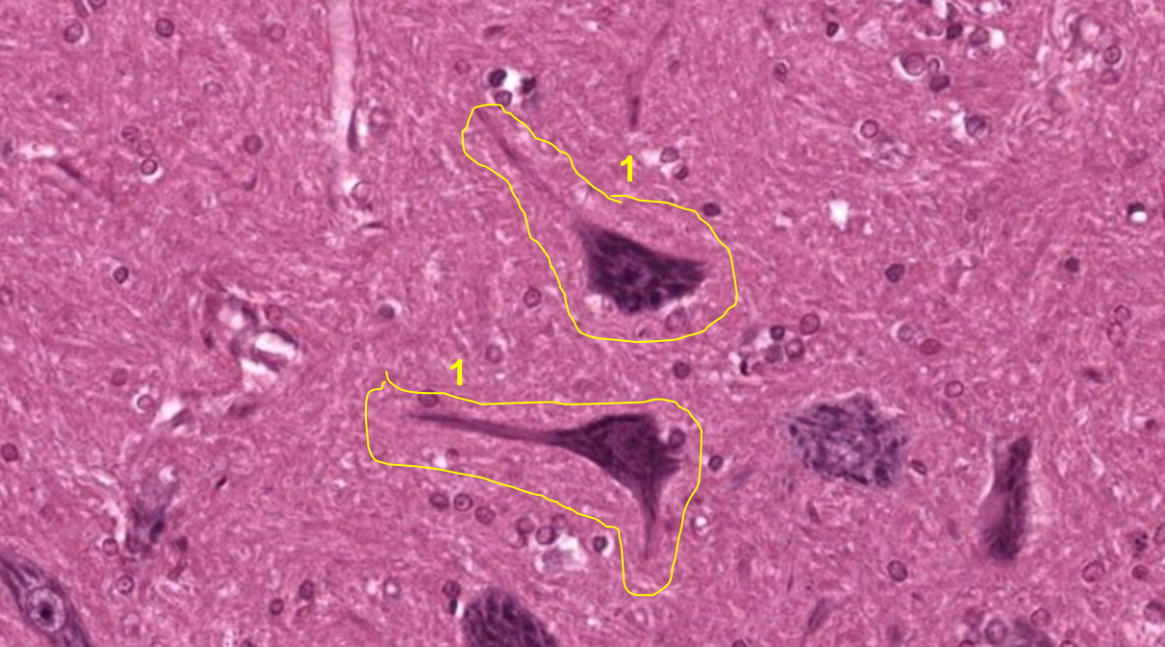

Substância cinzenta (1: Neurónio)

Medula espinhal (1: substância cinzenta; 2: substância branca)

Medula espinhal